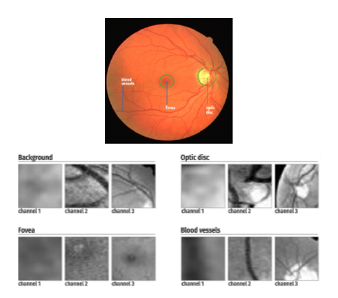

Por otra parte J .Tan, R. Acharya, S. Bhandary y K. Chua en (Tan et al. 2017) presentan un algoritmo de segmentación de imágenes oculares en donde se buscan identificar los vasos vasculares, la fóvea, el disco óptico y el fondo del ojo utilizando una red neuronal convolucional. En la figura 8 se observan las regiones de interés que se desean detectar; la red neuronal consta de 3 canales, esto se realiza para disminuir el costo computacional del programa usando imágenes más pequeñas pero brindándole más información a la red al tener una entrada múltiple. Para el entrenamiento se utiliza el algoritmo de back-propagation.

Los resultados en comparación a otros trabajos se muestran en la tabla 4, en donde se manejan 2 indicadores, el primero de sensibilidad que representa el porcentaje de pixeles identificados correctamente de la parte objetivo y la especificidad que es el porcentaje de pixeles que no fueron asignados a un grupo incorrecto.